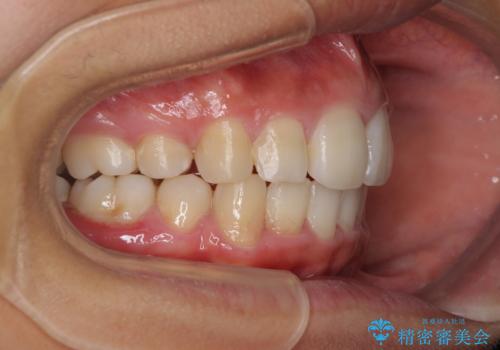

ワイヤーによる全体的ながたつきの矯正治療